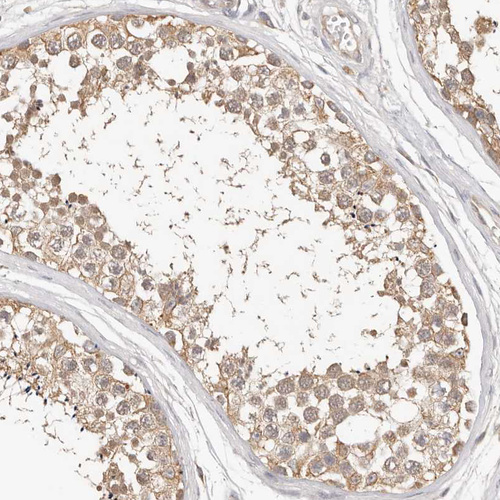

Immunohistochemical staining of human testis shows moderate to strong cytoplasmic positivity in Leydig cells.